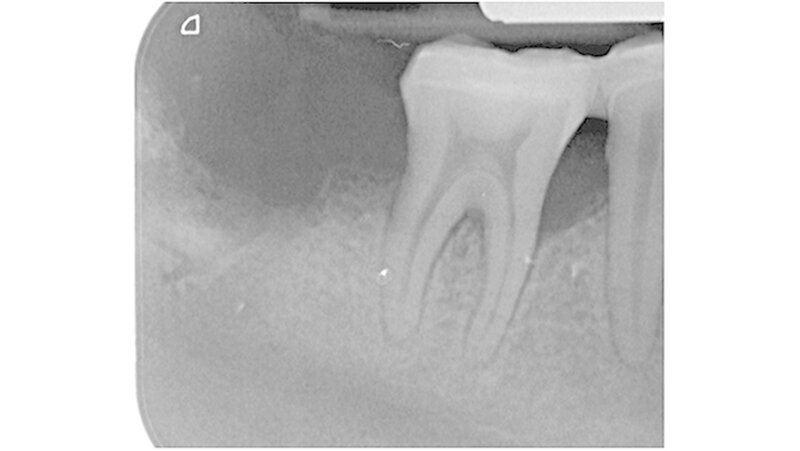

Die Aufnahme zeigte diesen Guttaperchapoint zwei Millimeter über den röntgenologischen Apex herausragen (Abbildung 1). Der Stift wurde wieder entfernt, eine Zwischeneinlage mit Calciumhydroxid appliziert und der Zahn temporär mit Glasionomerzement verschlossen. Die Patientin verließ die Klinik beschwerdefrei.